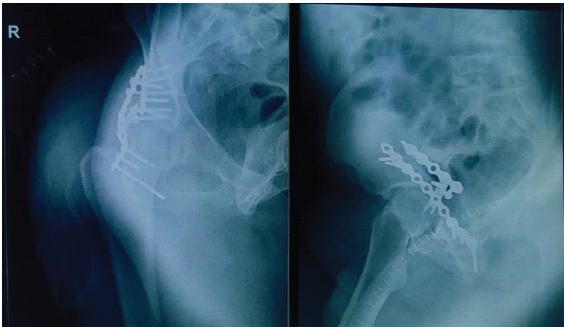

Under spinal anesthesia patient underwent open reduction and internal fixation of the acetabulum through the posterior Kocher-Langenbeck approach on deep dissection, we encountered a rare anatomical variation, the sciatic nerve dividing into common peroneal and tibial nerve below the piriformis (Figs. 3 and 4).

After noticing the sciatic nerve variation intraoperatively, with adequate pre-caution to prevent from the traction neuropraxia and nerve damage, internal fixation with plate osteosynthesis of the acetabular fracture was done.

During the hospital stay, he remained hemodynamically stable with no neurological deterioration. Pain was adequately controlled, and there were no immediate post-operative or in-hospital complications. Gradual mobilization was initiated as per protocol, with protected or non-weight-bearing advised on the affected limb. On follow-up visits, the patient showed progressive improvement in pain and hip range of motion. Long-term neurological and functional outcomes were normal. Radiological evaluation demonstrated satisfactory fracture alignment and healing. At the latest follow-up, the patient was ambulatory with support, had no neurovascular deficits, and reported improvement in functional outcomes, with no evidence of complications, such as infection, implant failure, or post-traumatic arthritis (Fig. 5).

Figure 5: Post-operative X-rays.